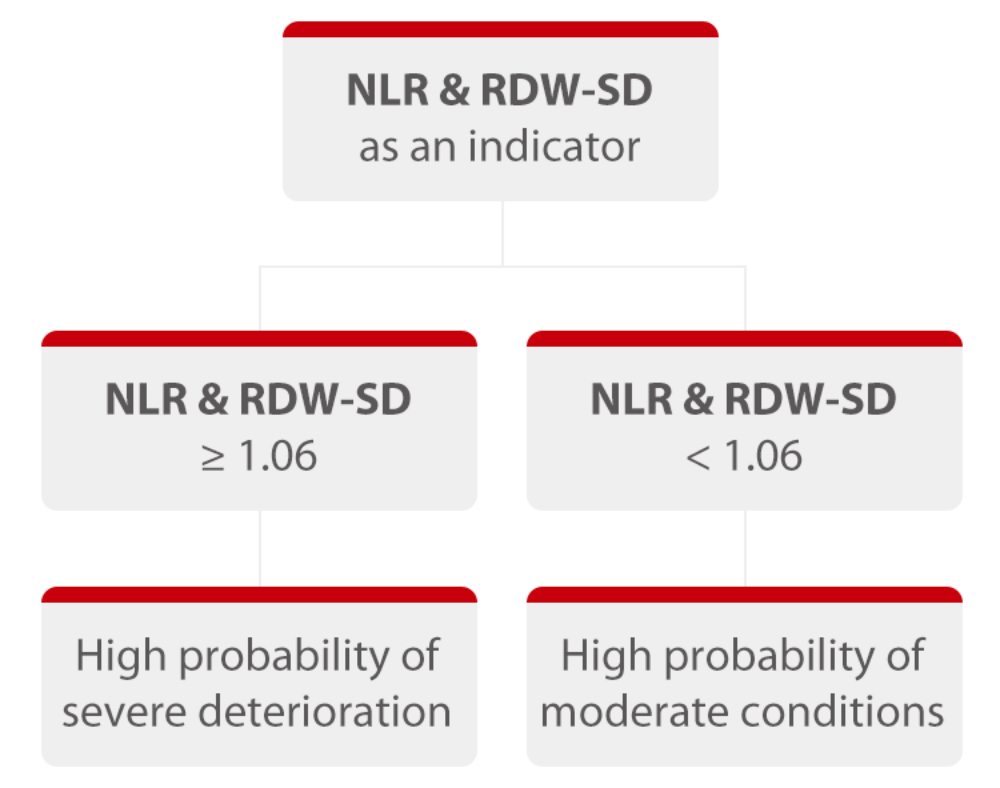

In view of the obvious RDW-SD differences between moderate and severe cases, a linear regression of NLR and RDW-SD is established, with an AUC at 0.94. When the cut-off value is 1.06, the sensitivity of distinguishing moderate cases from severe cases is 90%, and the specificity is 84.7%. That is, when its NLR & RDW-SD result is greater than 1.06, it is highly possible that the patient should be monitored closely in case of further deterioration and admitted to ICU if needed. This result can provide valuable information to facilitate faster, more accurate clinical decisions that leads to improved patient outcomes.

With NLR and RDW-SD results in focus, a linear regression and ROC curve analysis were introduced in order to establish the NLR & RDW-SD parameter as an indicator to identify severe cases. With an AUC reaching 0.94, this parameter can provide useful information to help doctors decide which category the patient should be put into and what corresponding treatment the patient should receive. However, it must be pointed out that this is a retrospective study and its applicability has yet to be validated with more clinical cases.